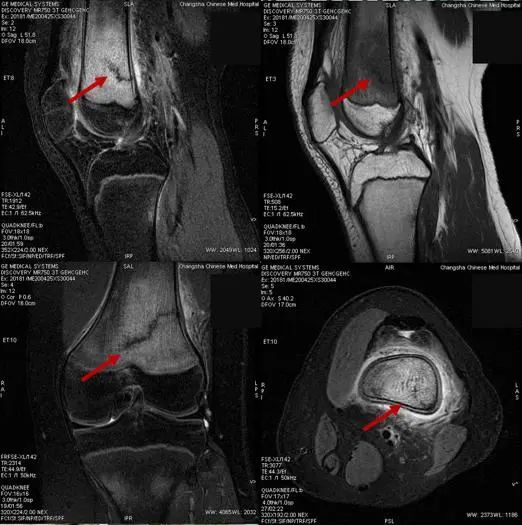

15岁的罗同学,因“右膝关节肿痛,加重1天”入院,在行膝关节磁共振成像检查时,发现“右侧股骨下段骨折并广泛骨髓水肿”。通过仔细询问病史发现,这名新近返校的初三学生,因邻近中考需要参加体育考试,每天都进行了一定强度的体育训练,最近几天出现膝关节疼痛明显加重,于是罗同学的妈妈带他到医院就诊。

很快,又有三名同学陆续来院就诊,他们的情况与罗同学完全一样,都是14~15岁的初中生,在学校参加跑步等体育锻炼后出现膝关节疼痛,并加重后就诊,经磁共振成像检查,被诊断为应力性骨折。

影像学检查能有效诊断应力性骨折,轻-中度应力反应早期X射线片表现可能不明显,但磁共振成像能有效发现骨膜及骨髓水肿。严重应力反应及应力性骨折在X射线片可见骨皮质增厚甚至骨折线影,而磁共振成像对骨膜与骨髓水肿范围显示更清晰。出现相关症状时,应及时进行磁共振成像检查。